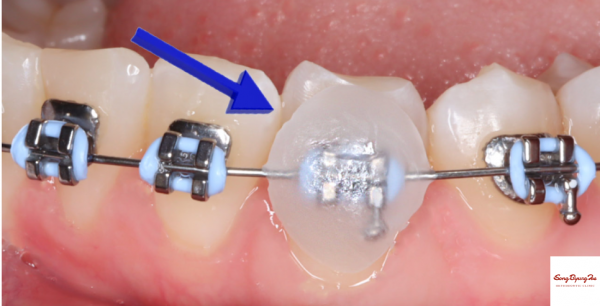

교정 치료 중 볼 안쪽이 헐거나 불편한 경우 중

가장 흔한 경우는 아래 그림과 같이

철사 끝이 빠져나와서 볼을 찌르는 경우입니다.